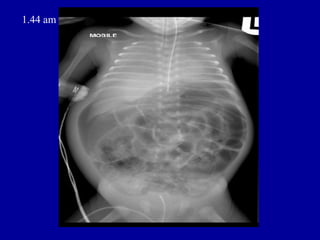

1.44 am

•   ORIGINAL REPORT

ORIGINAL REPORT • HISTORY • NEC, septic shock on CPAP, IA and IV lines. • REPORT • AXR - SUPINE AP • Compared with AXR taken 10 hours earlier. • The nasogastric tube is now seen projected over the left hypochondrium. There is • interval worsening of the gaseously distended intestinal loops. Faecal matter is • again seen in the proximal colon. No air or faecal matter seen in the pelvic cavity. • There is free extraluminal air within the peritoneal cavity, outlining the liver. • Rigler's sign is noted, consistent with intestinal perforation.